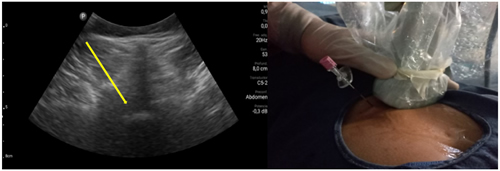

Los procedimientos fueron realizados en sala de operaciones, con vía venosa periférica y en posición decúbito ventral. Los mismos fueron realizados por el investigador principal (P. C.) con experiencia en la realización de procedimientos ecoguiados en la columna vertebral, utilizando la técnica paramediana en eje ecográfico corto. Se utilizó un ecógrafo portátil modelo Lumify marca Phillips, con transductor curvo de baja frecuencia. Fundas y gel ecográfico de la marca Pajunk® (Pajunk GmbH Medizintechnologie, Geisingen, Germany). En cada caso se identificó el espacio L4-L5 o L5-S1 mediante escaneo ecográfico de la columna lumbosacra en el plano transversal y longitudinal previo al inicio del procedimiento. Con la sonda ecográfica colocada en plano transversal o en eje corto, se realiza un habón anestésico 1 a 2 cm a un lado del transductor, correspondiente al lado del dolor radicular. La aguja de Tuohy ecogénica, 18 G (Tuohy Sono, 18G Pajunk® GmbH Medizintechnologie, Geisingen, Germany) de 9 o 12 cm según la contextura del paciente, se dirige en plano, en tiempo real, en sentido lateral a medial, entre la articulación facetaria por fuera y el ligamento interespinoso por dentro, hasta alcanzar el ligamento amarillo, en el espacio interlaminar elegido (Figura 1). El espacio epidural fue identificado mediante la pérdida de resistencia con suero fisiológico. Se registró la imagen doppler color durante la maniobra, como medida alternativa a la epidurografía con contraste (Figura 2). Posteriormente, 5 cc de contraste no iónico fue inyectado. Se consideró que fue alcanzado dicho espacio cuando el contraste se distribuye a lo largo del ligamento longitudinal posterior (Figura 2). 1 mg/kg de triamcinolona más 3 cc de lidocaína al 0,5 (hasta 10 cc de solución total) se inyectan en el espacio epidural.

Fig. 1. Escaneo ecográfico en eje corto o transversal del espacio L5-S1. La flecha amarilla muestra el punto de entrada de la aguja de Touhy en el abordaje paramedial y su trayecto. A la derecha se muestra la colocación de la aguja Sono Touhy en plano con el transductor curvo.

Fig. 2. Inyección de 5 a 10 ml de suero fisiológico con registro de la imagen doppler color, que se distribuye en el canal raquídeo, en una inyección epidural L5S1 paramediana derecha (imagen a la izquierda). Las flechas azules indican el trayecto de la aguja de Touhy. A la derecha se observa la confirmación con epidurograma de una inyección epidural L5S1 izquierda.